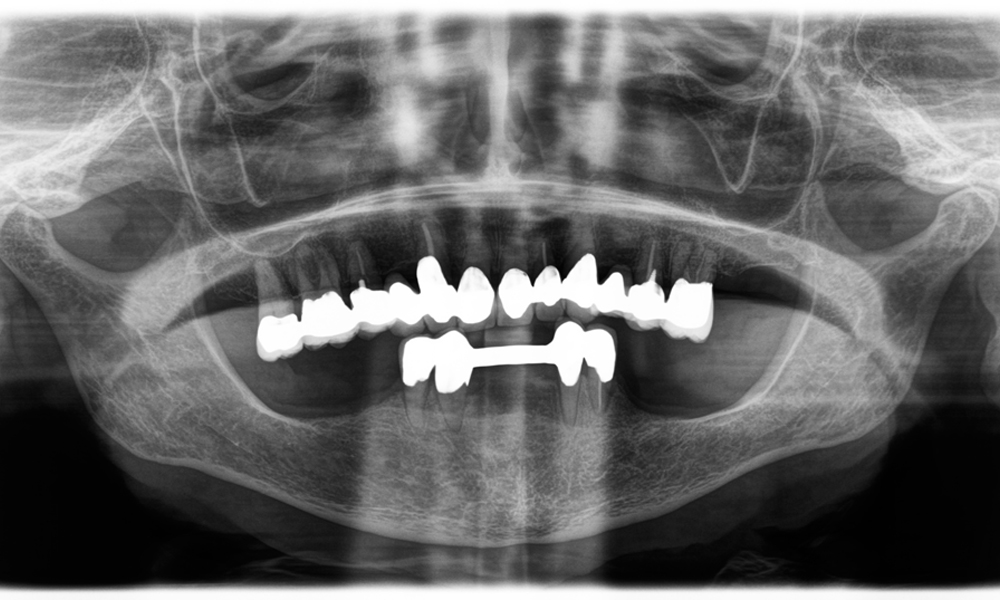

Предизвикателството беше да се премахнат дванадесет блок корони, изработени от сплав от неблагородни метали, без да се повредят подлежащите опорни зъби. Наконечникът беше използван за прецизно разрязване на керамичните слоеве и разделяне на металната конструкция с помощта на карбиден борер, което позволи минимално травматично отстраняване на короните. Само за 30 минути старите възстановявания бяха отстранени, което позволи подготовката на нова протеза, състояща се от циркониеви корони с пълна анатомична форма в задната част и фасети във фронталната зона. Резултатът беше цялостна реставрация, която осигури както функционален, така и естетичен успех (виж фиг. 1).